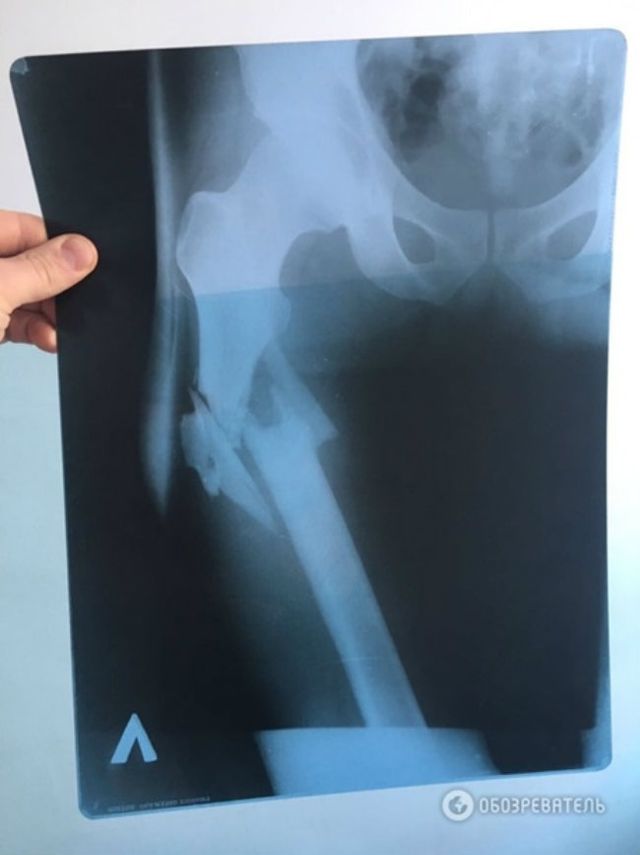

Нардеп від Народного фронту Сергій Пашинський збрехав, коли розповідав свою версію стрілянини у чоловіка, повідомляє Обозреватель з посиланням на джерело. Під час допиту лікар, який оперував постраждалого В'ячеслава Хімікуса, підтвердив, що на місці перелому у пораненого уламки кістки зміщені вниз від таза. Це підтверджує, що Пашинський вистрілив зверху в ногу Хімікусу, а не з положення лежачи, як нардеп стверджував раніше.

Видання також оприлюднило рентгенівський знімок простреленої ноги Хімікуса. Зважаючи на положення вхідного і вихідного отворів від кулі, можна припустити, що куля "йшла" зверху вниз.